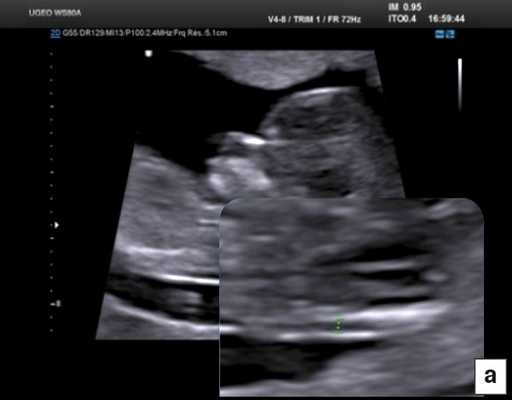

При эхокардиографии изучались четырехкамерный срез сердца плода (рис. 1) и срез через три сосуда (рис. 2). УЗИ проводилось трансабдоминальным датчиком, лишь при необходимости (затрудненная визуализация) использовался внутриполостной датчик. Четырехкамерный срез сердца плода при ультразвуковом сканировании трансабдоминальным датчиком визуализировался в 85% случаев, срез через сосуды - в 73%, при использовании трансвагинального датчика эти цифры существенно возрастали до 100 и 91% соответственно. Оптимизация пренатальной диагностики ВПС может быть достигнута путем строгого соблюдения основных методических правил. При оценке четырехкамерного среза плода необходимо оценить нормальное расположение сердца плода, исключив его эктопию (рис. 3), положение оси сердца плода, что не представляет никаких трудностей, нормальные пропорции и размеры камер сердца, движение створок атриовентрикулярных клапанов должно быть свободным, септальная створка трикуспидального клапана должна располагаться ближе к верхушке сердца (рис. 4). При оценке среза через три сосуда необходимо оценить взаиморасположение сосудов и их диаметр.

Рис. 1. Беременность 12 недель. Четырехкамерный срез сердца плода. Отчетливо видны камеры сердца.